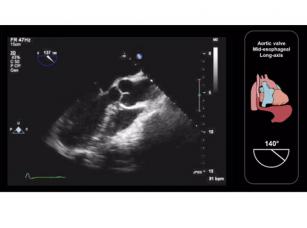

How to assess the aortic valve using TEE (mid-esophageal long-axis view) 10th Oct 2017 - Andrew R. Houghton, MD Learn how to assess the aortic valve (mid-esophageal long-axis view) using TEE. Taken from our Transesophageal ...